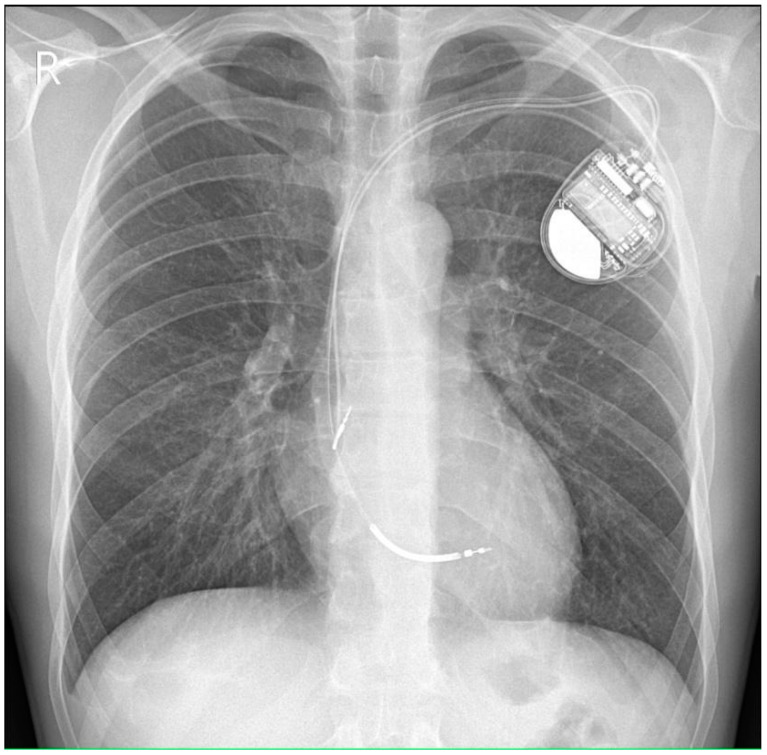

A dual-chamber cardioverter-defibrillator (ICD DR, he did not consent to have subcutaneous implantable cardioverter defibrillator) was implanted for the secondary prevention of sudden cardiac arrest and life-threatening ventricular arrhythmia (Figure 6). Antiarrhythmic treatment was intensified: the dose of metoprolol succinate was increased from 25 mg to 50 mg q.d.